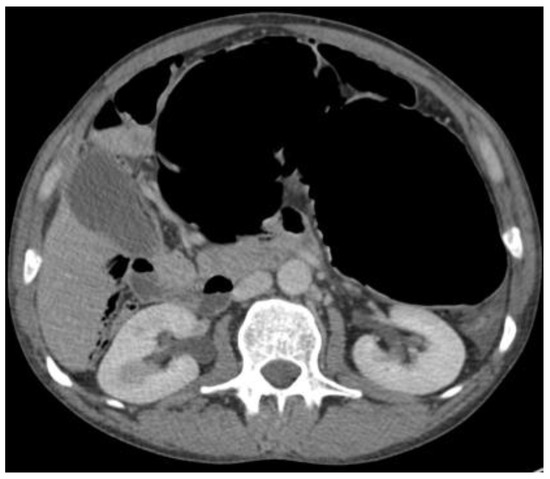

4.4.2. Computerised Tomography (CT) Scan

- CT scan confirms diagnosis in >90%

- Typical Radiological Signs are described

- Representative X-ray and CT images presented

| Abdominal radiograph | 11 (68.75%) | Five patients had CT as the only imaging. |

| Non-specific bowel loops/SBO | 5 (46%) | |

| Classical single loop of large bowel | 6 (54%) | |

| CT Abdomen and pelvis | 15 | One patient operated without CT. |

| CV not described | 1 | |

| CV correctly identified | 14 (93.3%) | |

| Caecal diameter >10 cm | 10 (67%) | |

| Whirl sign | 12 (80%) | |

| Split-wall sign | 13 (86.6%) | |

| X-marks-the-spot sign | 14 (93.3%) | |

| Double transition point | 13 (86.6%) | |

| Ileocaecal twist | 13 (86.6%) | |

| Central appendix | 11 (73.3%) |